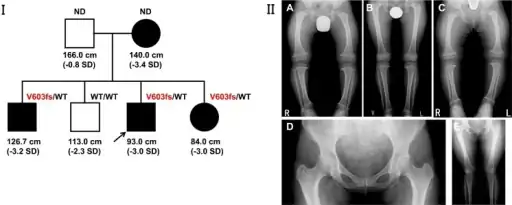

Unlike other "rickets syndromes", affected individuals have normal serum calcium, phosphorus, and urinary amino acid levels. Long bones are short and curved, with widened growth plates and metaphyses.[5]

a-c) Three siblings demonstrated metaphyseal irregularities hip/knee, coxa vara, bowlegs. d-e) the mother demonstrated coxa vara